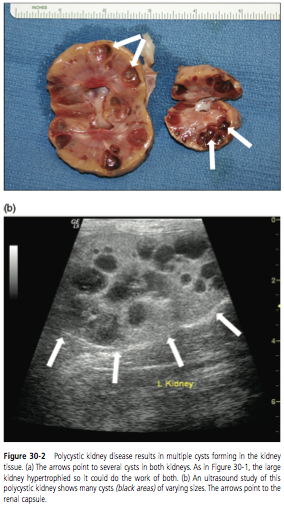

Urinary Tract Diseases

» Photos